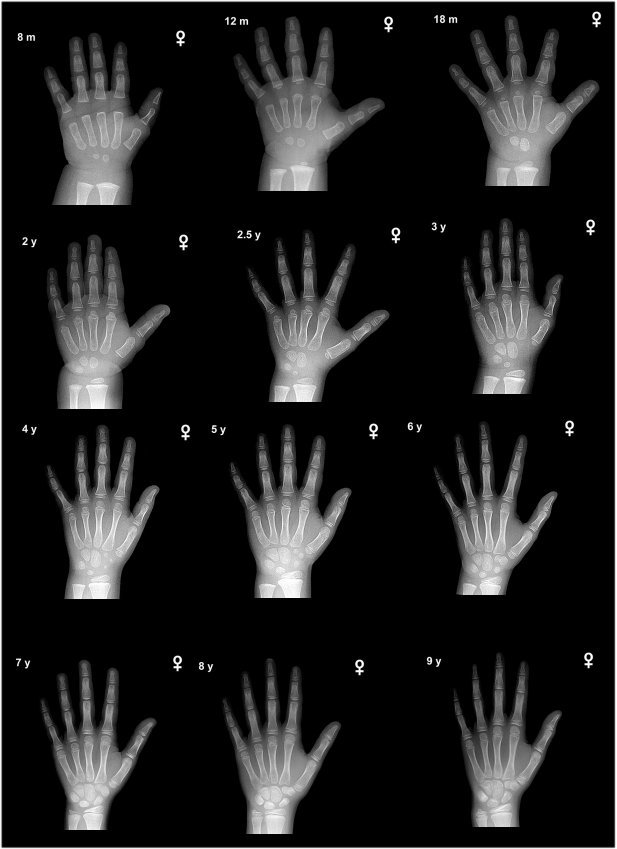

성장판 검사를 통해 성장판이 어느 정도 열려있고, 또 앞으로 얼마의 성장을 보일 것인가에 대한 예측도 중요하겠지만, 성장판 검사의 주 목적은 그 보다는 실제 아이의 나이와 뼈나이, 골연령과의 차이를 보기 위함이 더 큰 것입니다.

또한, 당장의 검사결과수치가 아니라 그 변화과정을 볼 수 있어야하기에 1년에 한 번, 또는 반년에 한 번, 경우에 따라서는 3달마다 검사를 반복하면서 골연령 진행속도를 보면서 성조숙증 여부를 체크할 수 있는 중요한 검사의 하나입니다.